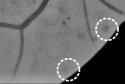

Figure 5 presents a random sample of the potential lesions retrieved by the method on a randomly selected image from DIARETDB1 training set. It is possible to see that most of false positive samples correspond to vascular branching or crossing points, vessel segments and beadings, scars due to laser photocoagulation or black spots of dirt in the capture device, as reported by Seoud et al. (2016). This setting underlines the importance of refine the candidates to remove false positives.

We also analyzed the viability of using the segmentation of the retinal vasculature as a potential source of information. As seen in Figure 5(a), most of the false positive detections are located in vessel crossings or beadings. Thus, we compute an initial vessel segmentation using the method reported in (Orlando and Blaschko, 2014, Orlando et al., 2017a), and postprocessing the output by removing every spurious connected component with less than pixels Orlando et al. (2017b). A morphological closing with a disk of radius 2 is afterwards applied to fill any gap due to the central reflex in arteries. Then, we measure the ratio of pixels in the candidate region that overlap with the segmentation, divided by the number of pixels in the candidate. Figure 6 illustrates the process of computing this feature. It can be seen that most of the false positive lesions located at the optic disc overlap with the resulting segmentation mask, and can be removed by this descriptor.